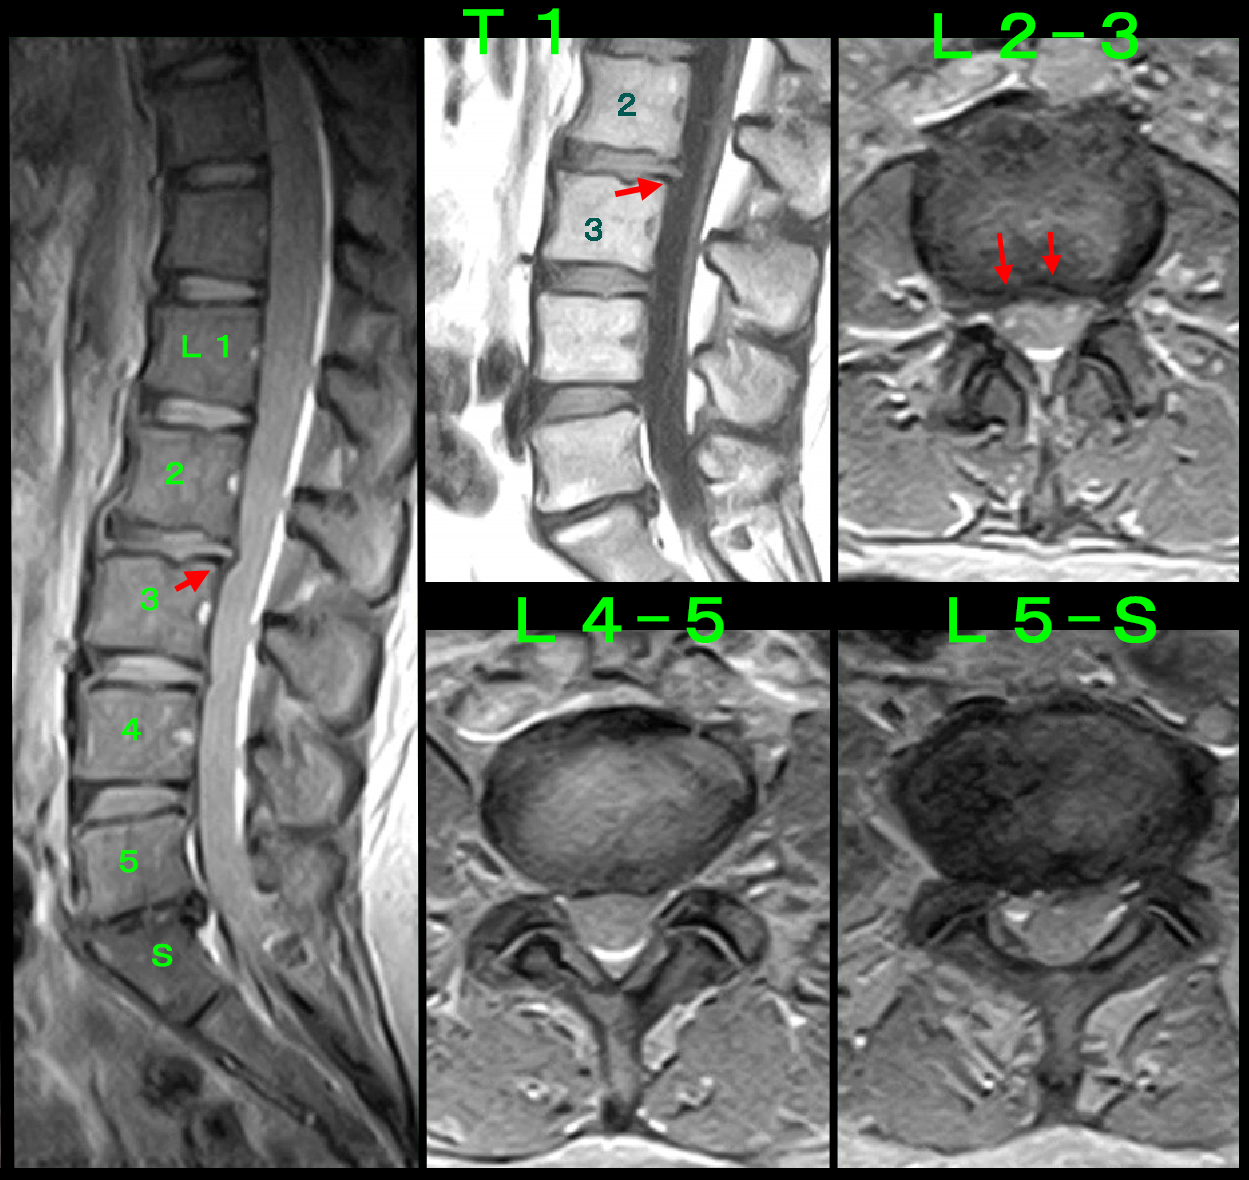

両膝レントゲン像

年齢からすれば膝の加齢性疾患(変形性膝関節症)が疑われます。しかし、レントゲン像は年齢に比して老化現象の所見はなく、

理学所見(診察での視診・触診などからの所見)でも変形性膝関節症を疑わせる所見は確認できませんでした。

変形性膝関節症であれば、A整形外科で実施されたヒアルロン酸製剤の関節内注入治療で一定効果が出ても良いはずです。

しかし、そうなっていません。私の診察では変性膝関節症の理学所見も確認されません。